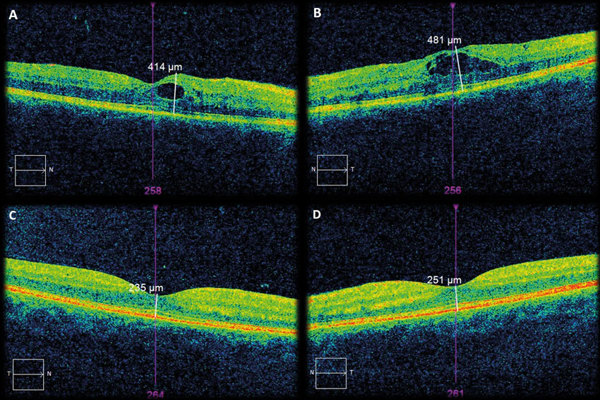

Diabetes macular oedema in pregnancy self-resolving postpartum